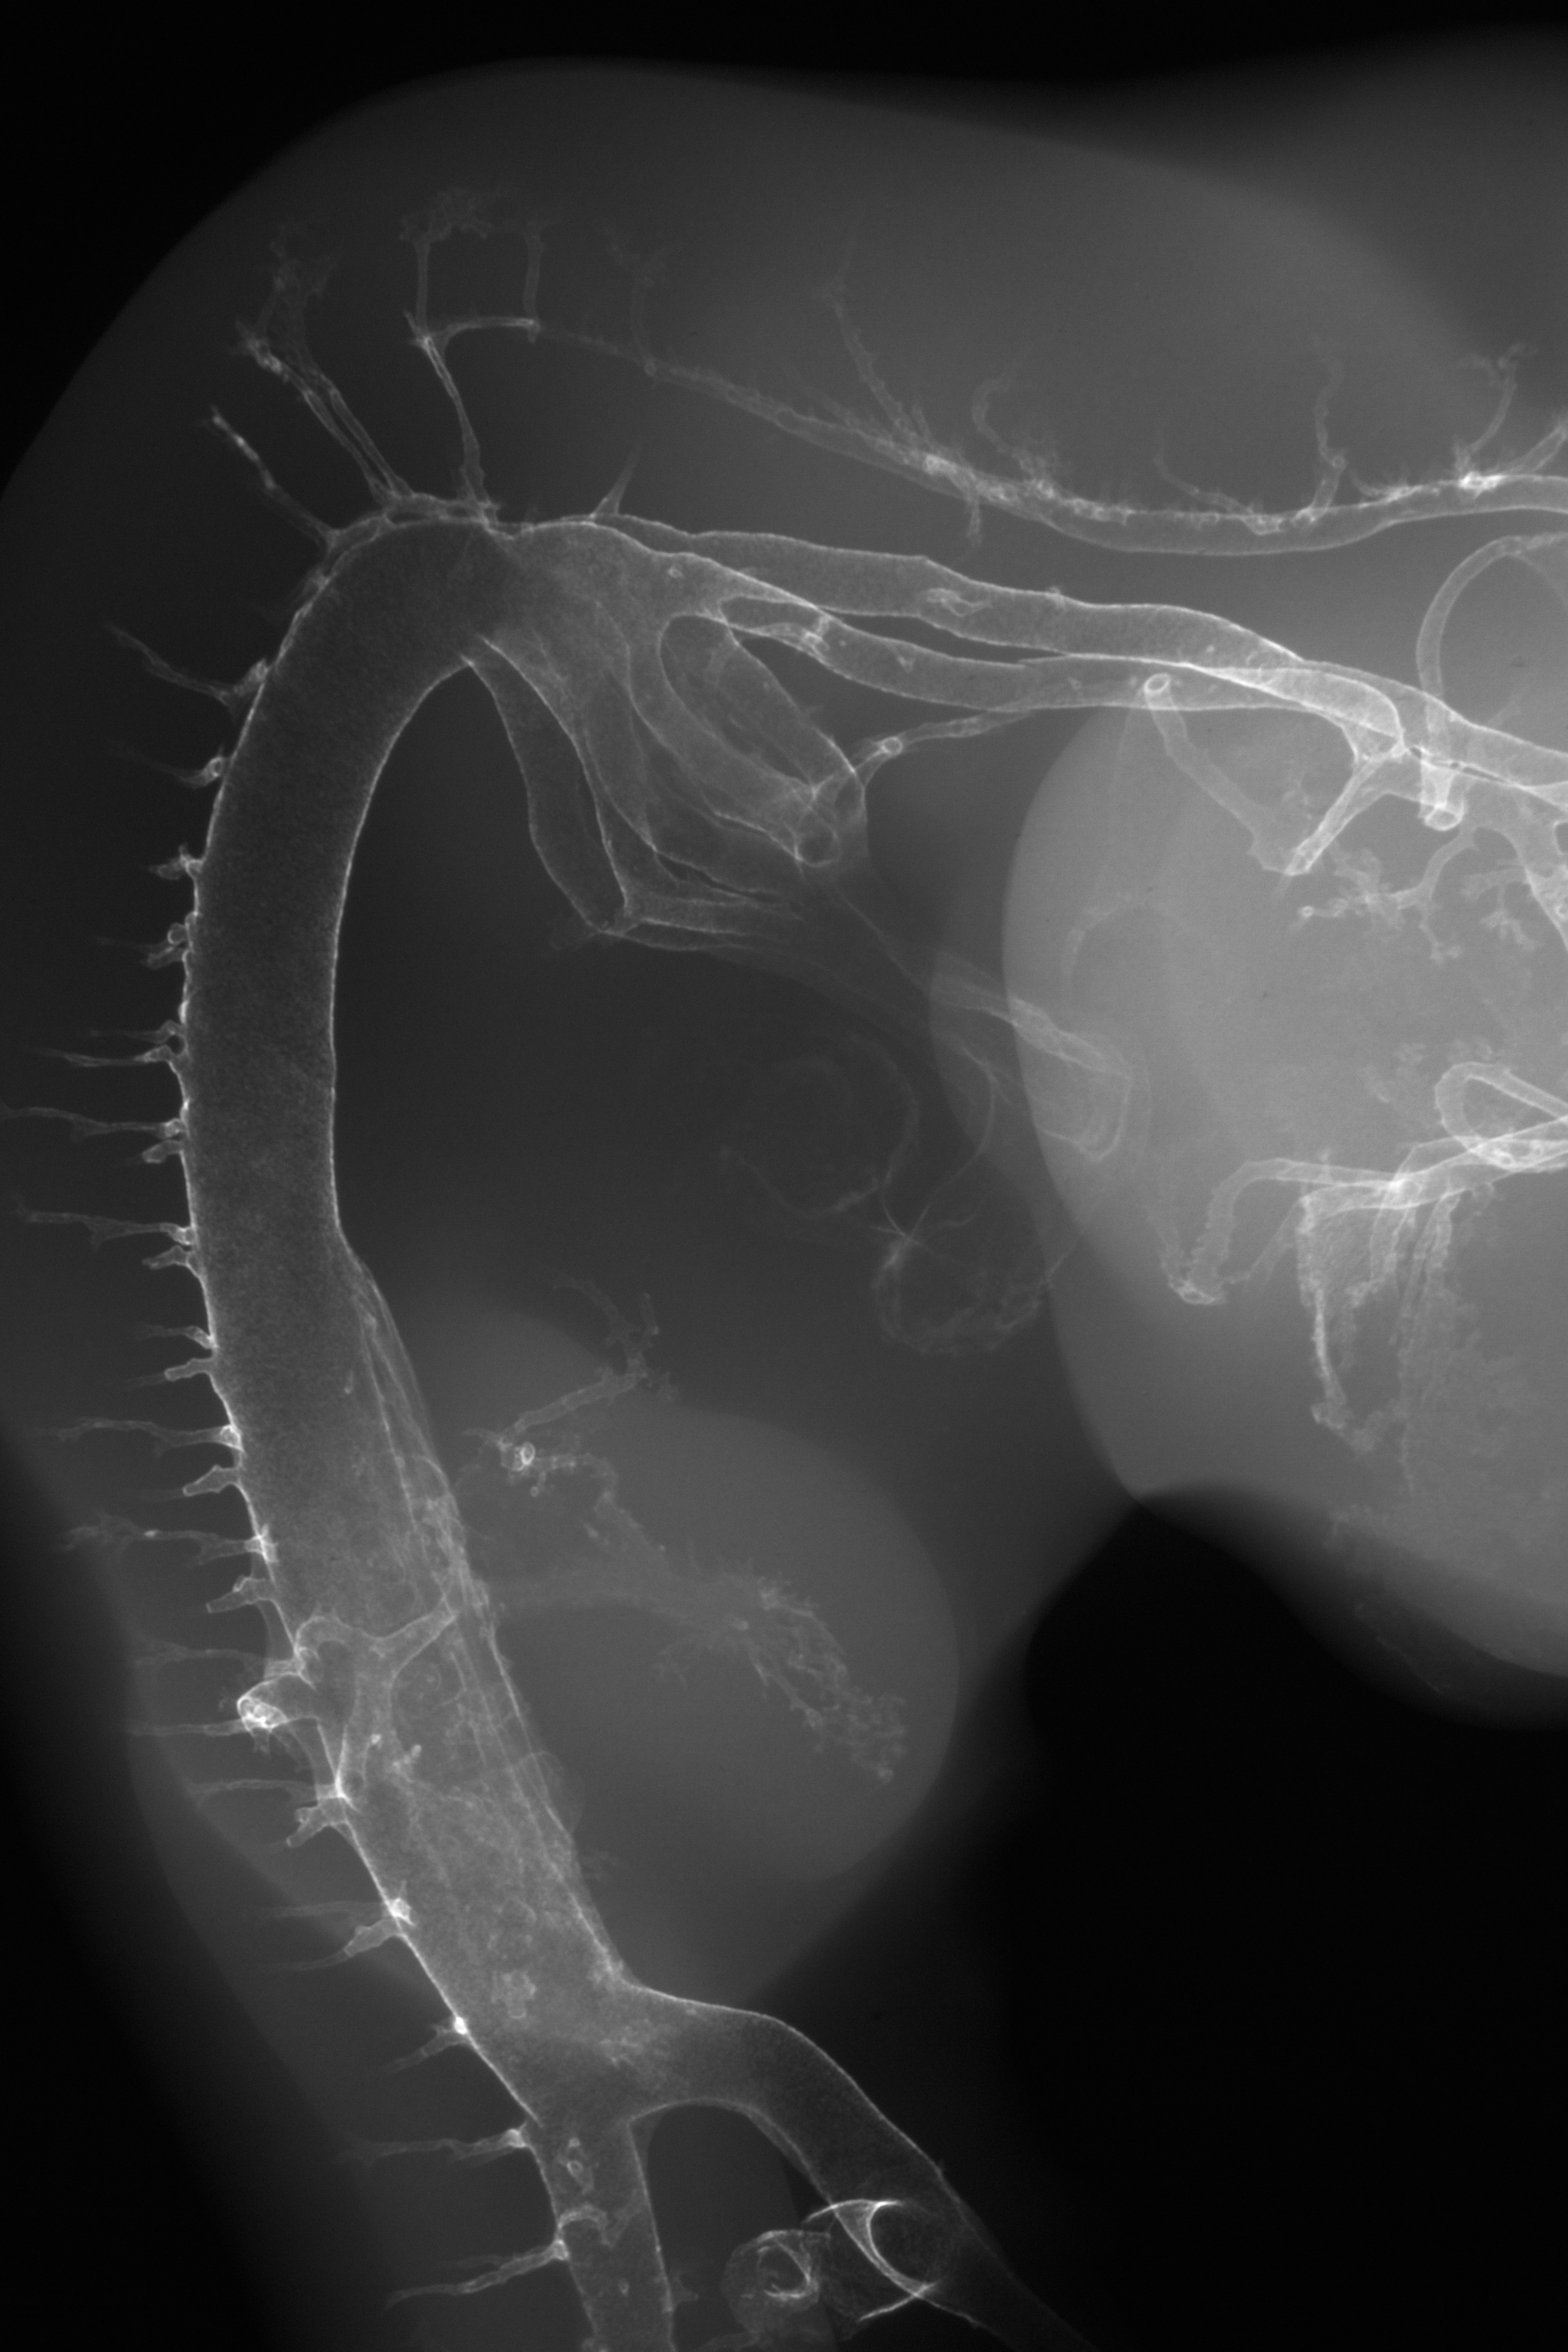

Chick Embryo Microangiography

Hamburger-Hamilton (HH) Stage 25 (approx. 4.5 - 5 days)

X-Ray Micrographs